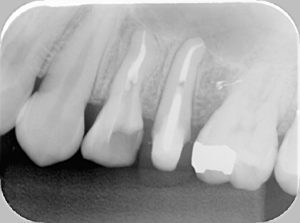

※根の再治療にて、根の先まで白いクスリがしっかり入っていて、膿の袋(黒い影)があったところも見えなくなっています!